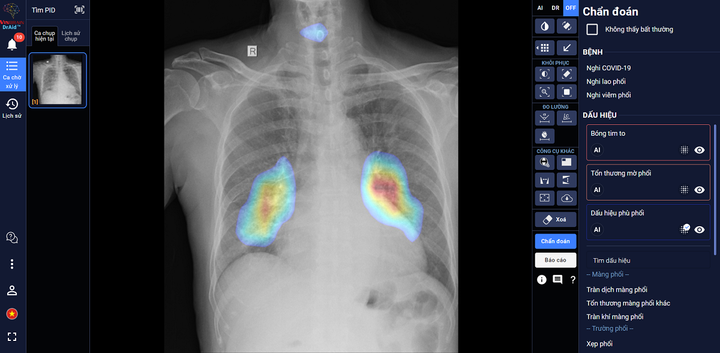

Đây là sản phẩm AI trợ lý bác sĩ với khả năng giải toàn diện bài toán COVID-19 từ hỗ trợ chẩn đoán tới tiên lượng điều trị dựa trên ảnh X-quang ngực thẳng, được ra đời dựa trên kết quả của Đề tài nghiên cứu của Cục Quản lý Khám chữa bệnh Bộ Y tế và công ty VinBrain là đồng chủ nghiệm đề tài.

DrAid có thể hỗ trợ chẩn đoán tới tiên lượng điều trị COVID 19 dựa trên ảnh X-quang ngực thẳng.

Bác sĩ Bệnh viện dã chiến Quận 11 (TP.HCM) sử dụng DrAid chẩn đoán COVID-19.